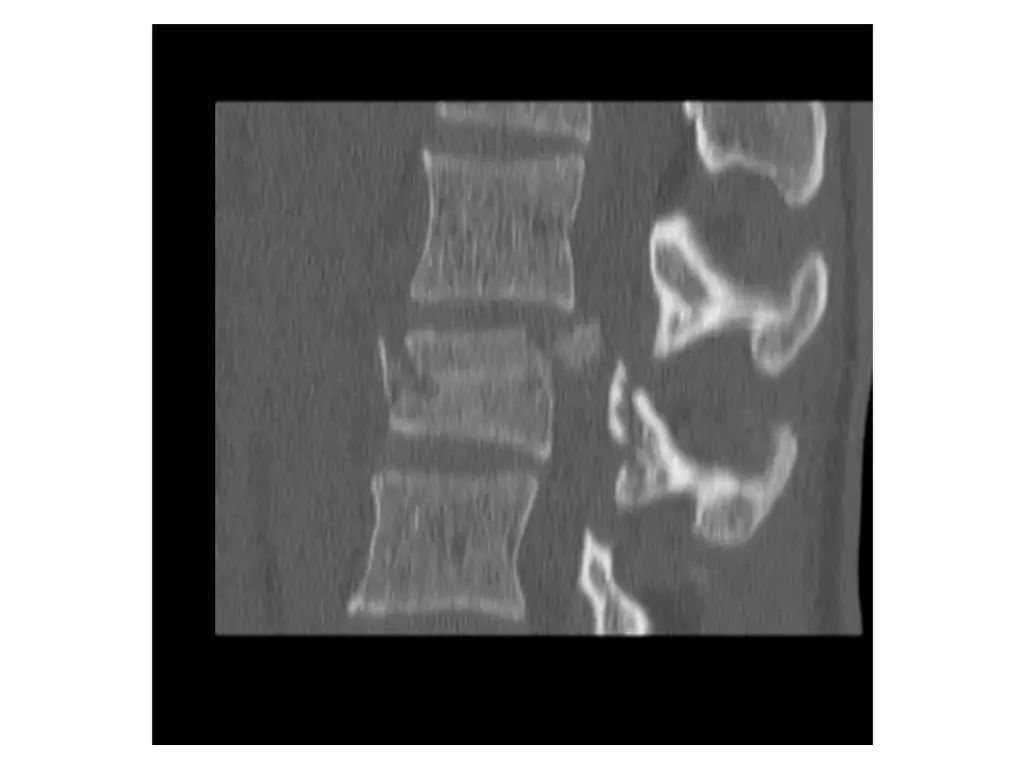

Imaging (Case 1) Midsagittal CT scan Parasagittal CT scan Axial CT scan Midsagittal STIR MRI scan

Imaging (Case 2) Lateral XR Midsagittal CT scan Parasagittal CT scan Axial CT scan

Imaging (Case 3) Lateral XR Midsagittal CT scan Parasagittal CT scan